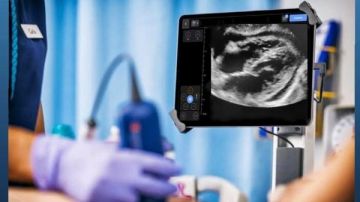

وتمكن الأطباء من تشخيص الحالة باستخدام تقنية السونار Point of Care Ultrasound، والتي كشفت عن وجود تجمع كبير للسوائل حول القلب، مما تسبب في ارتشاح قلبي أدى إلى حدوث اختناق القلب، وهي حالة طارئة تستلزم التدخل الفوري.

وأوصى الأطباء بضرورة إجراء تدخل عاجل لتجنب توقف عضلة القلب، حيث قادت الدكتورة ريهام كارم محمد، أخصائي الطوارئ، بالتعاون مع الدكتور بولا سمير، أخصائي القلب، عملية سحب السوائل من حول القلب باستخدام تقنية التوجيه بالموجات فوق الصوتية Ultrasound-Guided Pericardiocentesis، وتم تصريف نحو 1.5 لتر من السائل النزفي.